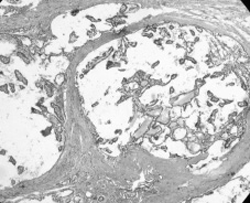

III.Васкулярная (сосудистая) инвазия. Несмотря на то, что некоторые авторы не выявили каких-либо отличий в клиническом поведении и прогнозе при ангиоинвазивных и неангиоинвазивных формах дифференцированных карцином [2], мы считаем, что сосудистая инвазия также имеет прогностическое значение (рис. 4). Так, у больных с отдаленными метастазами инвазия этих опухолей в кровеносные сосуды отмечена в большинстве случаев (70%).

Рис. 4. Начало сосудистой инвазии при фолликулярном раке щитовидной железы.

Окраска гематоксилином и эозином. X 100